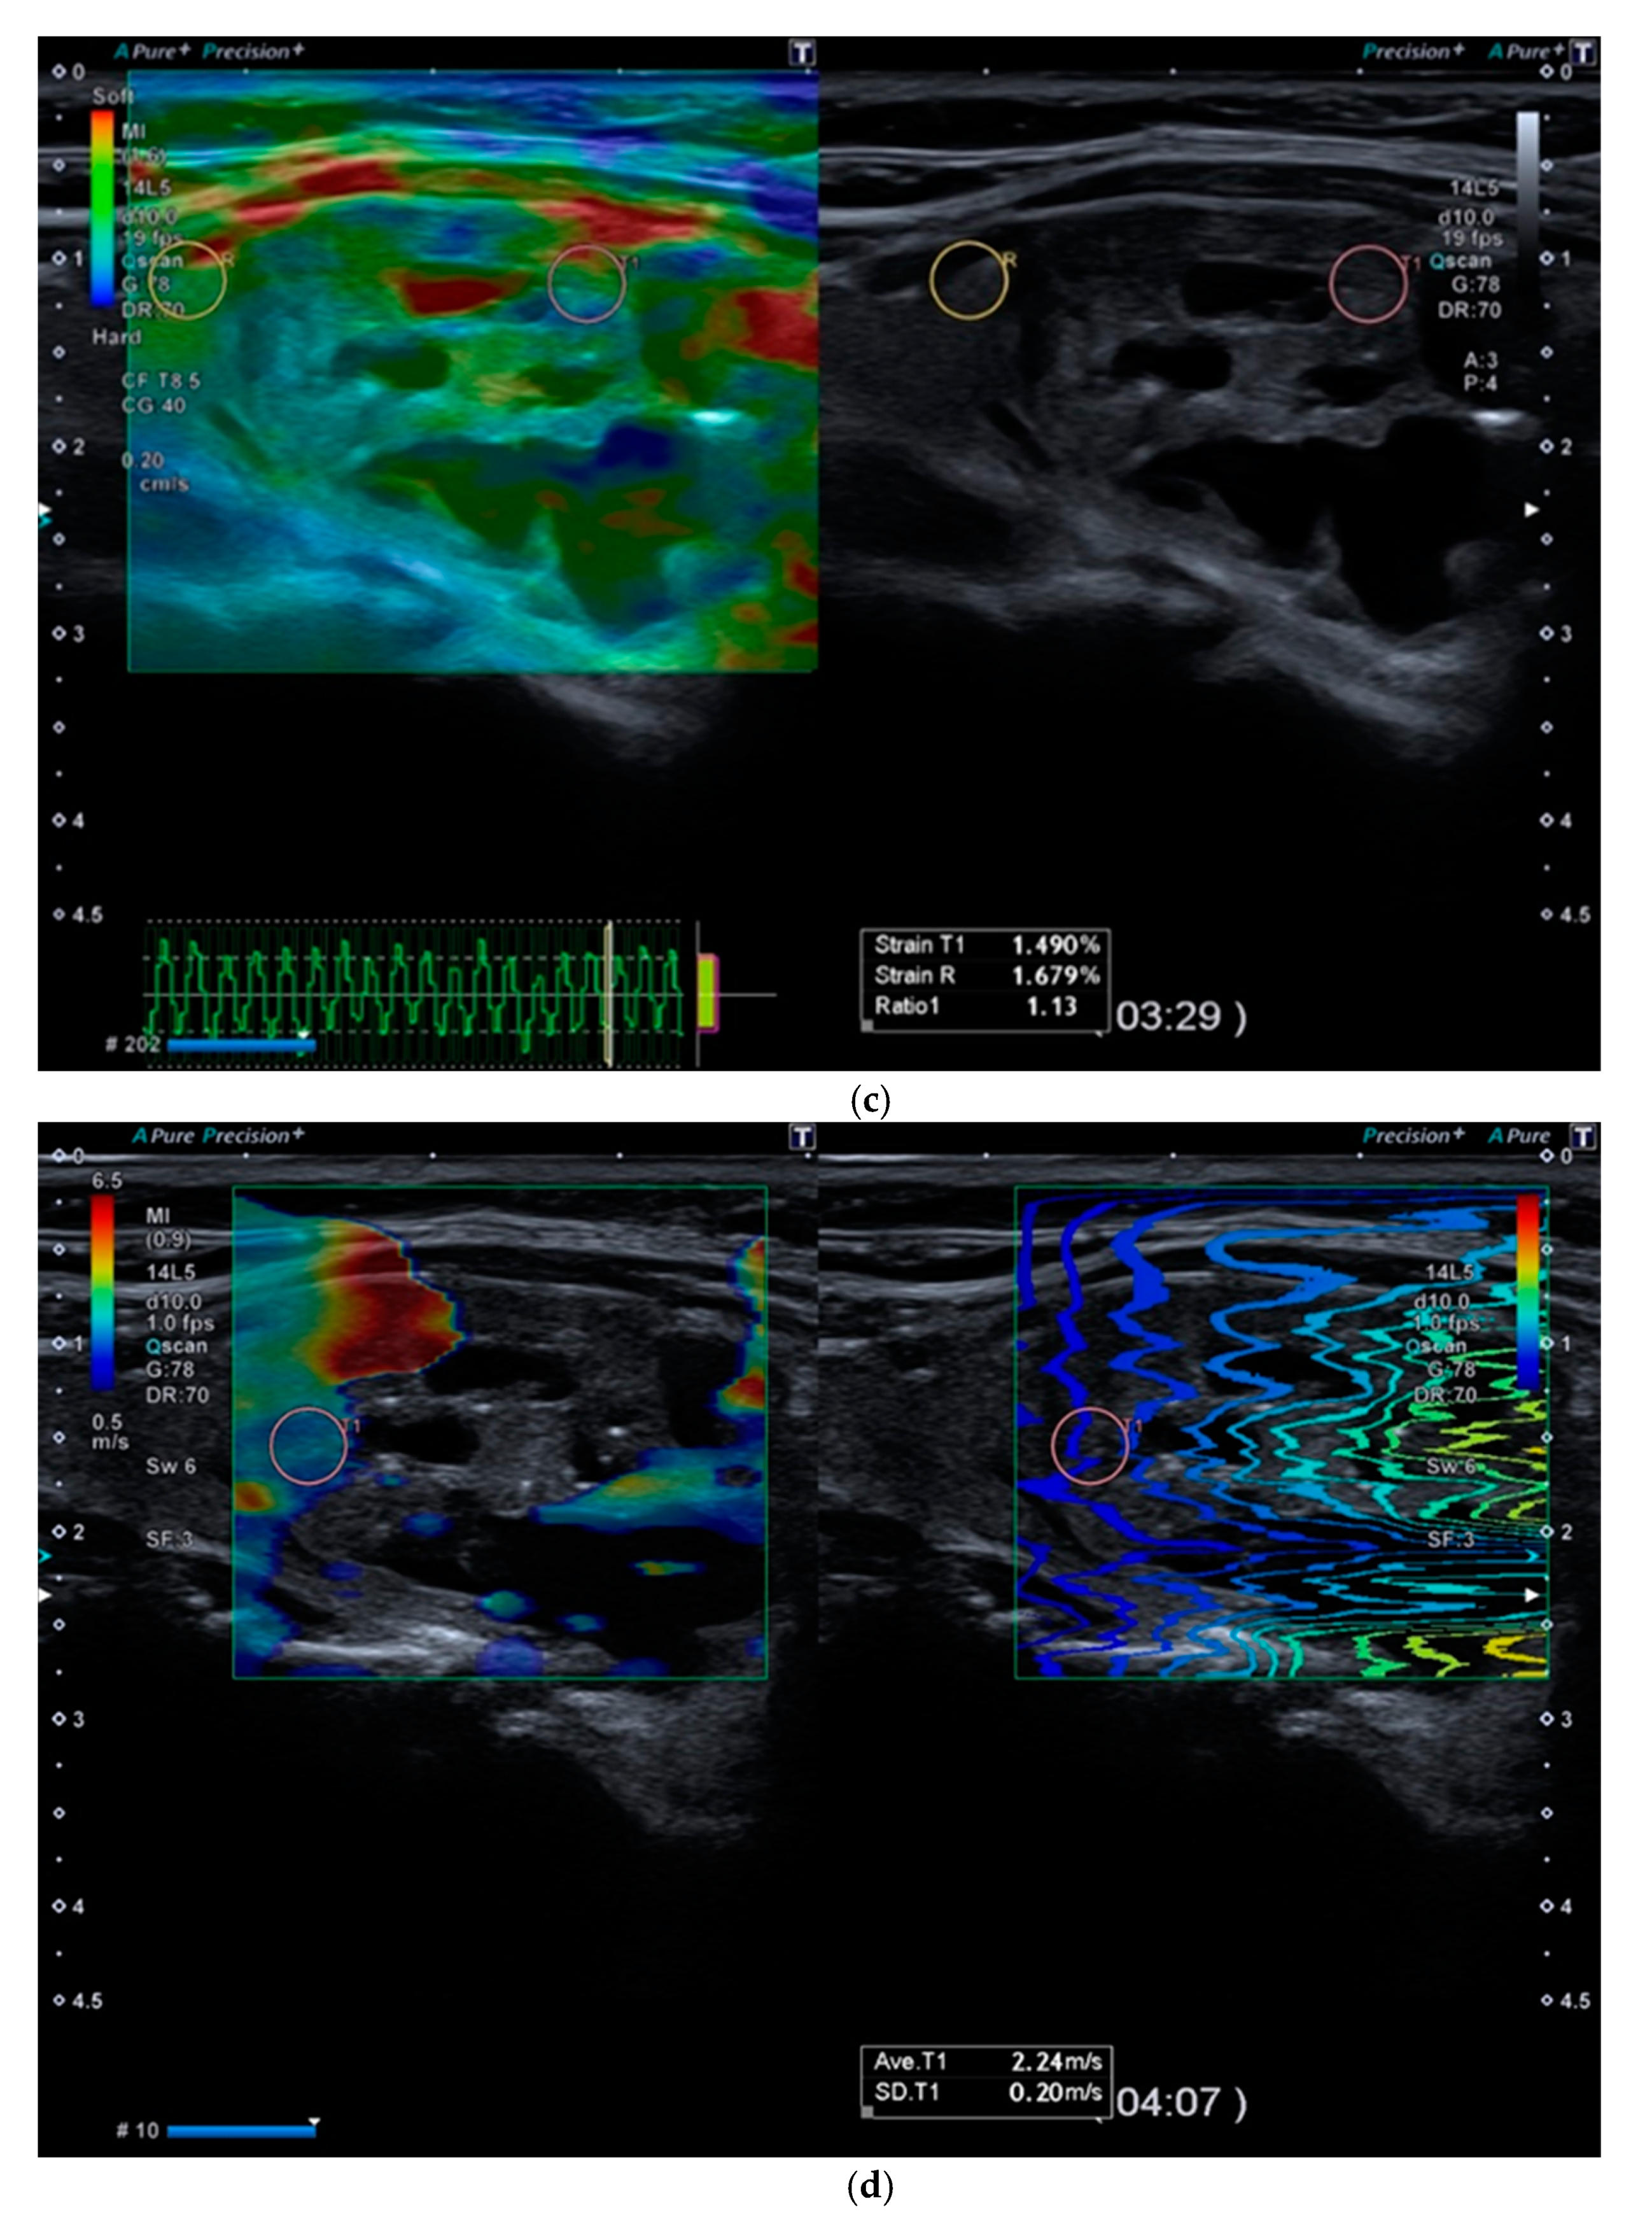

6. Multiparametric Ultrasound

Multiparametric Ultrasound (MPUS) Role for Indeterminate Thyroid Nodule Evaluation